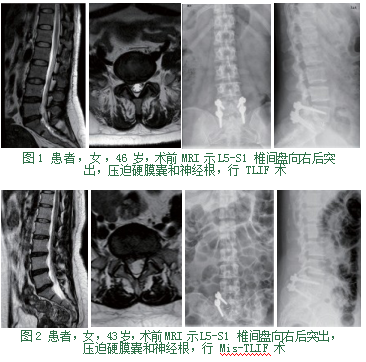

1.2手术方法。均行全身麻醉,取俯卧位,C-臂机定位,做好体表标记,常规消毒铺巾。①TLIF组:切口位于腰背部正中,依次切开皮肤、皮下组织及筋膜,剥离椎旁肌,显露椎板,于病变节段上下椎体两侧分别植入2枚椎弓根螺钉。咬除病变节段患侧上位椎体部分下关节突及下位椎体部分上关节突、黄韧带,棉片保护神经根下行椎间隙及侧隐窝彻底减压,选用合适cage植骨后置入椎间隙,透视满意后安装连接棒并适度加压固定。切口两侧旁放置引流管各1根,逐层缝合,关闭切口。本组采用单侧减压,双侧椎弓根螺钉固定。

(图1)②Mis-TLIF组:切口位于腰椎棘突患侧,依次切开皮肤、皮下组织及筋膜,钝性分离多裂肌与最长肌间隙至椎板,置入定位导杆,逐步放置扩张套管,建立Quadrant通道,适度撑开扩张通道,显露视野,按TLIF方式行患侧减压,合适植骨cage置入病变间隙,于该间隙上下椎体同侧植入2枚椎弓根螺钉,C-臂机透视位置满意,安装连接棒,切口旁放置引流管1根,余处理同TLIF组。本组采用单侧减压,单侧椎弓根螺钉固定。(图2)两组患者术后24 h后引流低于50 mL,拔除引流管,根据患者情况,鼓励并指导患者早期佩戴腰围下床活动。